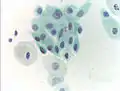

_Smear.jpg.webp) Micrograph of a normal pap smear

Micrograph of a normal pap smear Micrograph of a Pap test showing a low-grade intraepithelial lesion (LSIL) and benign endocervical mucosa. Pap stain.